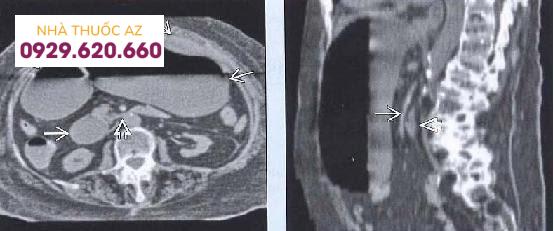

CT bụng và vùng chậu cho thấy: tá tràng bị chèn ép (mũi tên đen) giữa động mạch mạc treo tràng trên (mũi tên màu đỏ) và động mạch chủ bụng (mũi tên màu xanh).

Tá tràng bị giãn rộng (mũi tên), bị thắt đột ngột bởi động mạch mạc treo tràng trên.